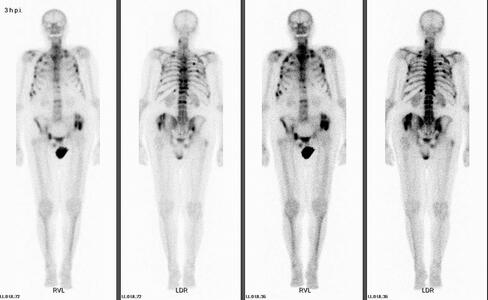

Mit der Methode ist die bildliche Darstellung des Knochenstoffwechsels in Knochen und Gelenken möglich. Es können entzündliche, degenerative sowie bösartige Veränderungen festgestellt werden, oftmals noch bevor sie im Röntgenbild zu erkennen sind. Ebenso lassen sich auch Verletzungen des Knochens, sowohl frische als auch monatelang zurückliegende, nachweisen, insbesondere wenn sie röntgenologisch nicht dargestellt werden können. Ein unauffälliges Knochenszintigramm schließt eine Erkrankung des Knochens weitgehend aus.

Zu Beginn der Untersuchung wird Ihnen eine geringe Menge einer radioaktiven Substanz (Tc99m markierte Phosphonatverbindung) in eine Vene gespritzt. Diese Substanz beteiligt sich am Knochenstoffwechsel und reichert sich insbesondere an der Knochenoberfläche vorübergehend an. Zur bildlichen Darstellung werden Aufnahmen mit einer Gammakamera ca. 3 Stunden nach der Injektion durchgeführt, Dauer ca.1 Stunde, in der Regel liegend auf dem Rücken. Sie erleichtern uns den Ablauf, wenn Sie am Tag der Untersuchung auf metallische Gegenstände am Körper oder in der Kleidung (z.B. Schmuck, Schüsselbund) verzichten.

Bei bestimmten

Fragestellungen, insbesondere zur Beurteilung möglicher entzündlicher

Veränderungen, wird zusätzlich die Weichteildurchblutung untersucht und

dazu ergänzende sogenannte Frühaufnahmen erstellt. Bei dieser

Mehrphasen-Szintigraphie erhalten Sie die Spritze, während Sie unter der

Kamera liegen oder sitzen und die Frühaufnahmen werden gleich nach der

Injektion durchgeführt.